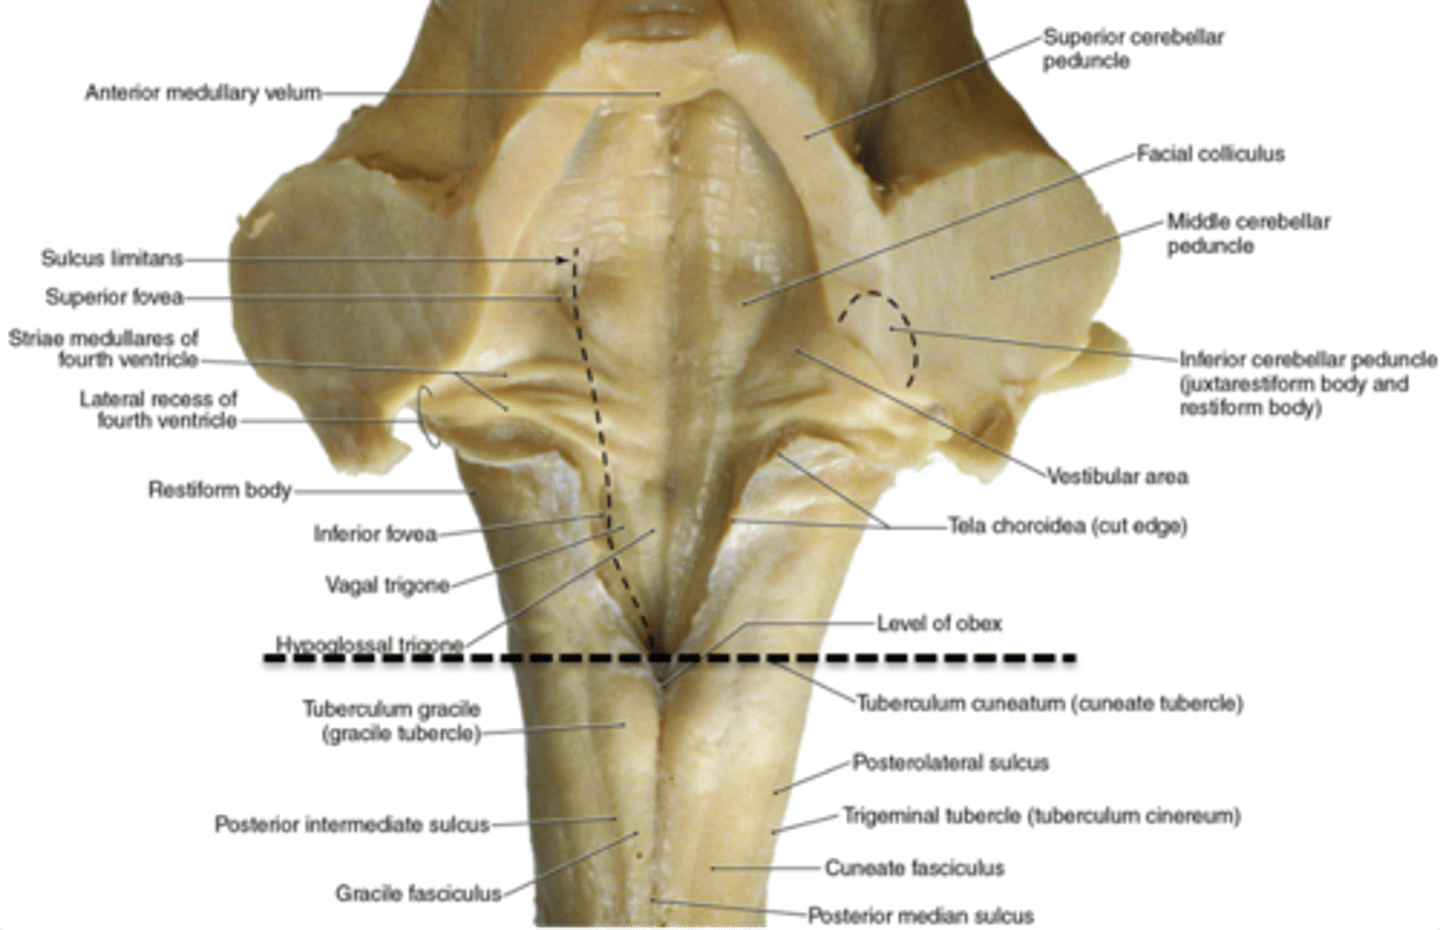

what are the 2 tubercles found on the closed (caudal) medulla?

1. gracile tubercles (more medial, touch/proprioception from lower body)

2. cuneate tubercles (more lateral, touch/proprioception from upper body)